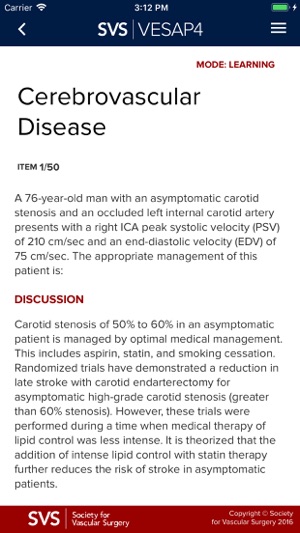

VESAP4 has over 500 questions and includes detailed discussions and references for each question. You may use this product in Learning Mode as often as you like. You will not earn CME credit or MOC self-assessment credit in Learning Mode; however, you will be able to review a rationale for the responses and will access available abstracts in PubMed.

In Learning Mode, you can view the correct answer to each question, the rationale and references. At the end of each session, you may save your answers and return at a later time or you may elect to end the session and view your score. You may use this product in Learning Mode as often as you like and you make take all or part of the exam.